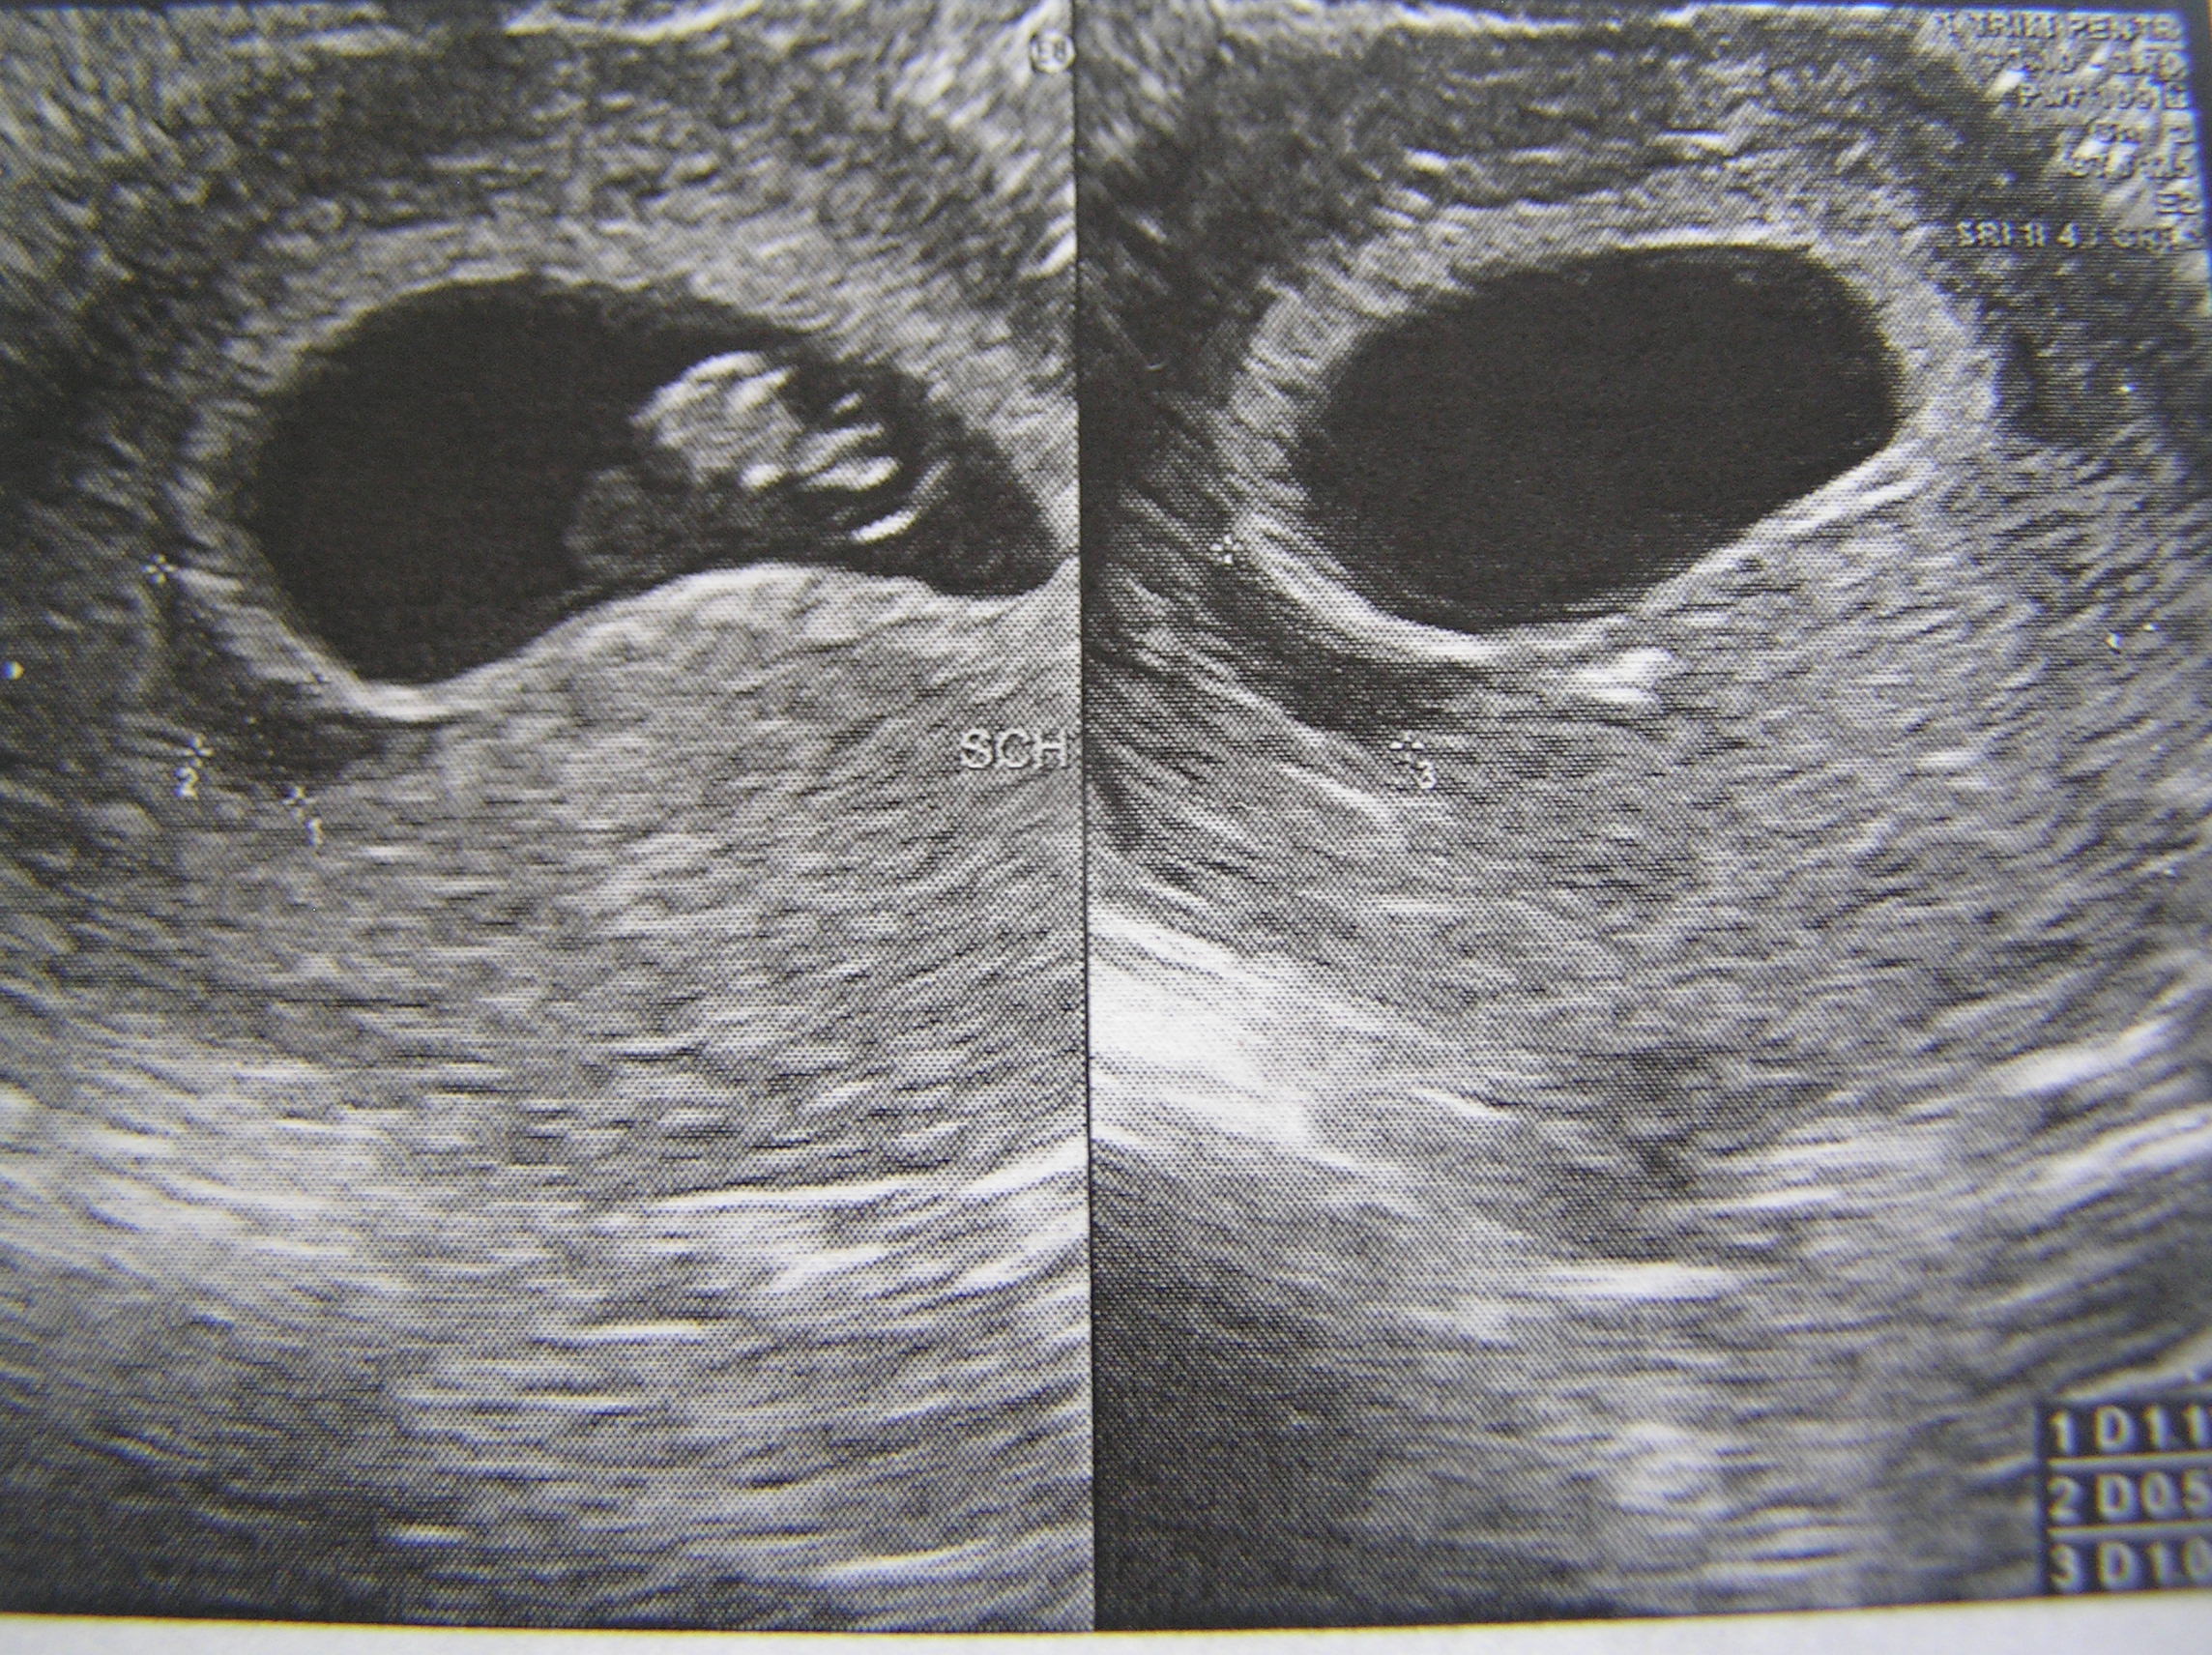

УЗИ 10 недель беременности двойня

Снимок УЗИ 9-10 недель беременности